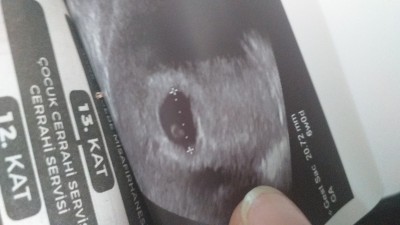

kızlar 6 haftalıkken 20.72 normal mi dr kesede hafif düzensizlik var dedi cihazdan öyle gözükmüş olabilir mi

Evet cihazdan kaynaklı olabilir ultrason başlığını bastırınca kesenin şekli yamulabiliyor

Cinsiyeti ramzi teorisine gore kiz :)

Ramzi teorisi var cnm %90 tutuyor ordan bak